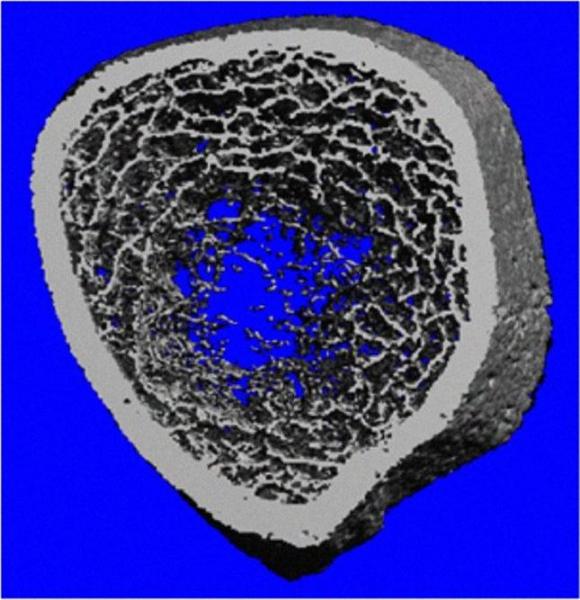

Con los médicos de la Clínica de Intestino Delgado del Udaondo, que dirige el doctor Julio Bai, seleccionaron a 30 mujeres jóvenes con enfermedad celíaca recién diagnosticada y a 22 con otros trastornos gastroenterológicos. En el IDIM hicieron análisis de laboratorio, una densitometría e imágenes de la tibia y el radio de cada una de las 52 jóvenes. Con un equipo que genera imágenes tridimensionales de un corte transversal de los huesos, por primera vez se pudo visualizar por qué aumenta el riesgo de fracturas en las mujeres celíacas premenopáusicas.

“Detectamos una pérdida significativa del hueso trabecular, una red ósea interconectada que en las participantes sin la enfermedad tenía una trama cerrada, pareja, con uniones del mismo tamaño -contó Zanchetta-. En las celíacas, las trabéculas estaban afinadas hasta desconectarse por la pérdida de calcio.”

Al año, las mujeres habían recuperado un 9% del tejido trabecular. “La intervención aumenta el volumen de las trabéculas -precisó Zanchetta-. No es tanta la diferencia con las mujeres sin enfermedad celíaca, pero aún es estadísticamente significativa. Pero, en este primer año, mejoraron los valores de vitamina D y la salud ósea general. Pensamos que van a seguir mejorando. Son los primeros resultados.”